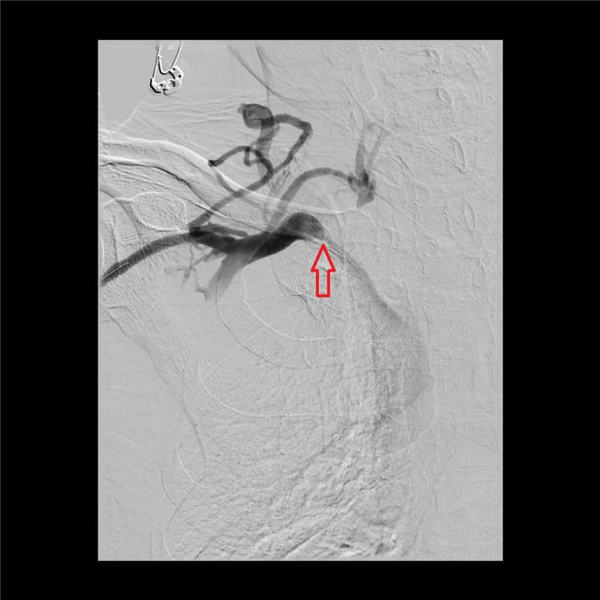

陈力强和赵庆和两位主任经过精心研讨方案,首先通过血管造影,发现右上肢动静脉瘘到上腔静脉共有三处血管明显狭窄(下图红色箭头所示),特别是右锁骨下静脉汇入上腔静脉处更明显,此处血管狭窄造成透析时血液回流障碍、右肩局部血管压力增高,由此引发右肩疼痛。